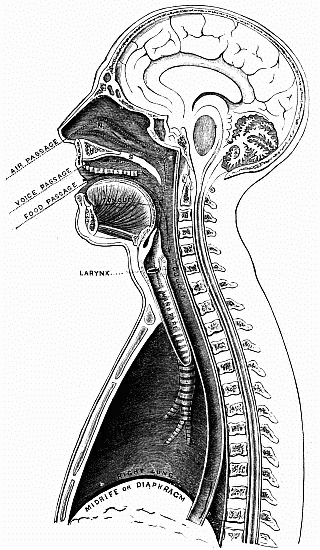

| I. | General view of vocal organ | facing title |

| 1.— | THE BELLOWS. |

| Represented by the Lungs. Pl. I (Frontispiece), L. | |

| 2.— | THE WINDPIPE. Pl. I, w. |

| 3.— | THE VOICEBOX or LARYNX. Pl. I, v. |

| 4.— | THE RESONATOR. |

| Represented by (a) The Upper Part of the Throat, or Pharynx, pl. I, P; (b) The Mouth, pl. I, M; (c) The Nose, pl. I, N. |

The Chest (pl. III) is an air-tight chamber, which is narrower above than below. It is formed by the spine at the back, twelve ribs (pl. III, 1 to 11, the twelfth not visible on the drawing), with their inner and outer muscles on either side, the breast-bone (pl. III, B B) in front, the root of the neck at the top, and the midriff or diaphragm (pl. I, M) at the bottom.

The Windpipe (pl. I, W).—Having examined the bellows of our vocal organ, we next notice the windpipe, by means of which the air is carried into and out of the lungs. It is an elastic tube kept open by 18 or 20 rings which do not quite meet at the back. It enters the lungs by means of two smaller tubes, which in their turn branch out very much like the roots of a tree, until their ramifications end in the microscopic cells of the lungs. The windpipe is capable of being slightly elongated or shortened, and narrowed or widened, and its interior is covered with a mucous membrane, which, as its name implies, is continually kept in a moist state.